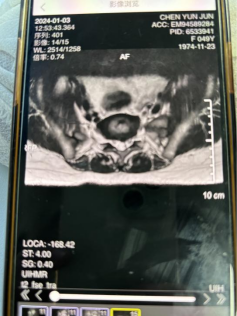

二、病史:患者20余年前无明显诱因下出现腰痛,期间至当地医院治疗断断续续,症状时轻时重。1月前自觉右侧臀部疼痛,伴有右下肢放射痛麻木,甚则放射至脚趾,前往恩泽医院就诊,诊断为“腰椎间盘突出症”行腰椎MRI提示:“腰4-5椎间盘右后脱出,腰5/1椎间盘左后突出;腰4-1椎管狭窄;腰4-5终板炎;腰椎退行性变”。近期患者自觉症状逐渐加重,故来我院针灸科门诊求诊。

四、辅助检查:外院腰椎MRI提示:“腰4-5椎间盘右后脱出,腰5/1椎间盘左后突出;腰4-1椎管狭窄;腰4-5终板炎;腰椎退行性变”。